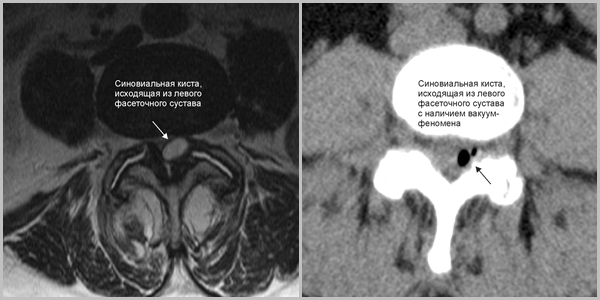

Формирование периартикулярных образований происходит в области фасеточных суставов и обычно имеет приобретенный характер. Кисты этого типа могут возникать на фоне дегенеративно-дистрофических заболеваний и травм.

Часто встречается подкожная киста, которую можно легко обнаружить при пальпации пораженного участка позвоночника, хотя такие дефекты встречаются довольно редко. В процессе развития периартикулярные новообразования выходят из полости фасеточного сустава и постепенно теряют с ним связь.

Этот дефект крайне редко вызывает выраженный корешковый синдром. Периартикулярные каверны могут быть синовиальными и ганглионарными. В первом случае новообразование имеет синовиальную оболочку. Такие дефекты чаще всего формируются в шейном и поясничном отделах, так как эти зоны подвержены физическим нагрузкам. Ганглиональные дефекты, в свою очередь, не имеют синовиальной оболочки внутри.

Синовиальная

Такие кисты образуются из синовиальных оболочек суставов позвоночника. Постепенно они увеличиваются, заполняясь синовиальной жидкостью. Синовиальные кисты могут достигать значительных размеров и формироваться в любом сегменте позвоночника.

Синовиальные кисты позвоночника могут быть вызваны постоянным воспалением и износом суставов позвоночника вследствие дегенеративных заболеваний, таких как остеоартрит, или травмы. При синовиальной кисте позвоночника происходит выпячивание ткани в фасеточных суставах — соединениях костей позвоночника.